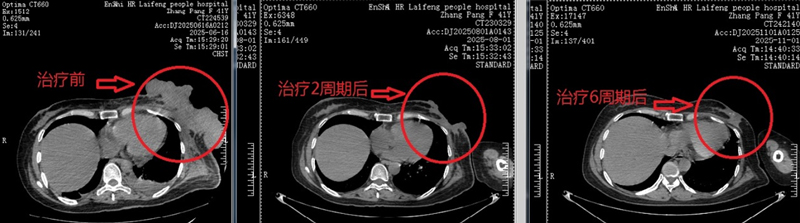

从今年6月到10月,经过6个周期的规范治疗,奇迹在张女士身上悄然出现。影像学检查显示,其乳腺原发病灶及周围转移结节明显缩小;更令人欣喜的是,长期困扰她的乳房皮肤溃烂面大幅愈合,生活质量得到了根本性改善。